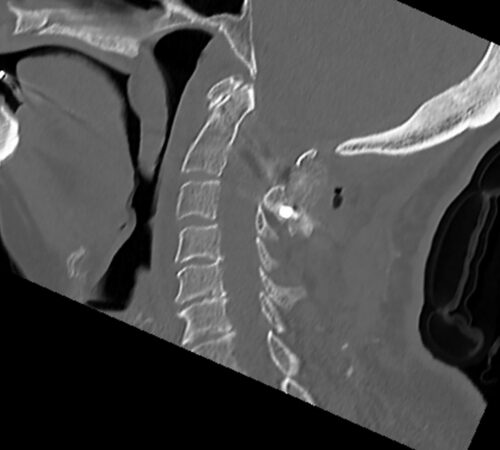

• Zlomenina dens axis (obratel C2), která je typická ve starším věku. Ošetření pomocí zadní stabilizace.

Pacienty s poraněním míchy nebo ostatních nervových struktur operujeme, co nejdříve to dovoluje celkový stav pacienta, ideálně do 4-6 hodin od úrazu. Při komplikovaných úrazech je primární zajištění životně důležitých funkcí (oběh, ventilace, edém mozku atd.), následuje operace páteře. Poranění obratlů kranio-cervikalního přechodu (hlava+C1+C2) je vzhledem k riziku postižení dechového centra nutné považovat rovněž za život ohrožující.

Jednotlivé procedury se při operačním výkonu prolínají a fungují společně. Pro zajištění primární pooperační stability ze zadního přístupu používáme v krční i torakolumbální oblasti vnitřní fixátory. Jejich součástí jsou šrouby případně háky a spojovací tyče překlenující poraněný páteřní segment. Z předního přístupu jsou nejčastěji aplikovány kostní štěpy nebo klece přemostěné dlahou v krční oblasti, expandibilní klece a fixátory v torakolumbální oblasti. Všechny fixační prvky jsou vyrobeny ze slitiny titanu, která omezuje negativní stíny na vyšetření CT a jsou MR kompatibilní. Pro dosažení trvalé kostní stability používáme přemostění poraněného obratle nebo obratlů kostními štěpy z lopaty kosti kyčelní nebo syntetickou náhradu (trikalciumfosfát, hydroxiapatit).